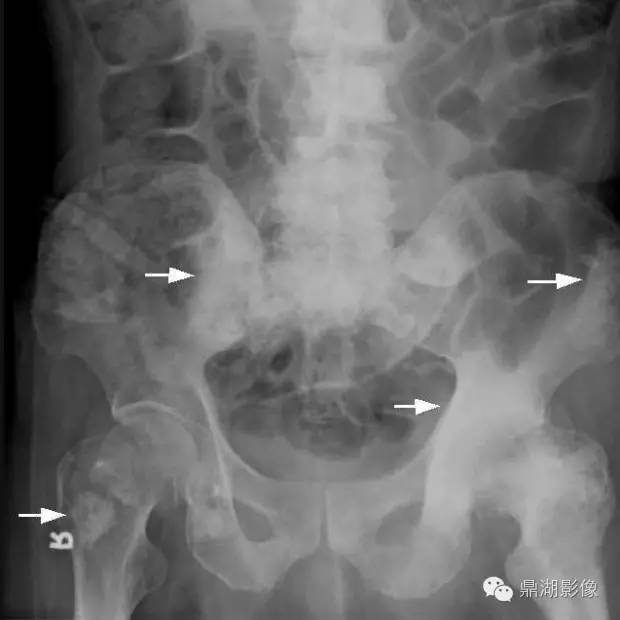

70岁,男,前列腺癌患者

X线片表现:成骨性转移表现为在骨外型没有改变的骨背景上出现圆形或椭圆形致密影,有时呈地图状,边缘不规则,多数病灶可融合成片,也有病灶累及大部分或整个骨,有时在成骨性病灶边缘散在少量溶骨性破坏。密度呈棉絮样增高。前列腺癌骨转移多较典型,结合临床,诊断一般不难。

实验室检查,血清碱性磷酸酶常增高,约占80%~85%;血清酸性磷酸酶也明显增高,对诊断前列腺癌骨转移有重要价值。